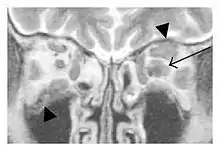

Infraorbital nerve enlargement (IONE) is considered to be a particularly suspicious sign of IgG4-ROD, but seems to occur only when inflammation is in direct contact with the infraorbital canal.[10] IONE is defined as the infraorbital nerve diameter being greater than the optic nerve diameter in the coronal plane.

![]() Enlargements in the left inferior rectus muscle and infraorbital nerve (arrow) in a 65-year-old man with a serum IgG4 of 404 mg/dL.[1] (T2-weighted MRI) |

![]() Swelling of the left superior and lateral rectus muscles, a mass lesion around the left optic disc (arrow), and enlargements of the left supraorbital nerve and the right infraorbital nerve (arrow heads) in a 60-year-old man with a serum IgG4 of 463 mg/dL.[1] (T1-weighted MRI) |